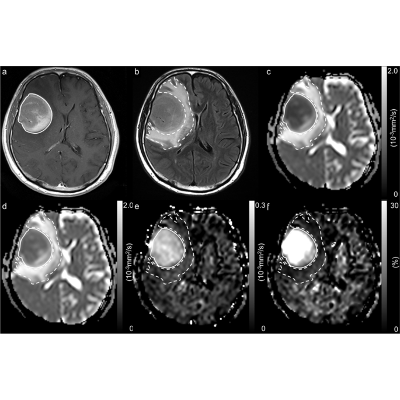

Primary diffuse large B-cell lymphoma (DLBCL) of the central nervous system (CNS) is a rare and aggressive disease, recently acknowledged as a distinct entity by the 2017 World Health Organization classification of hematopoietic and lymphoid tumors. Management of patients with newly diagnosed PCNSL is complex and requires a multidisciplinary approach....